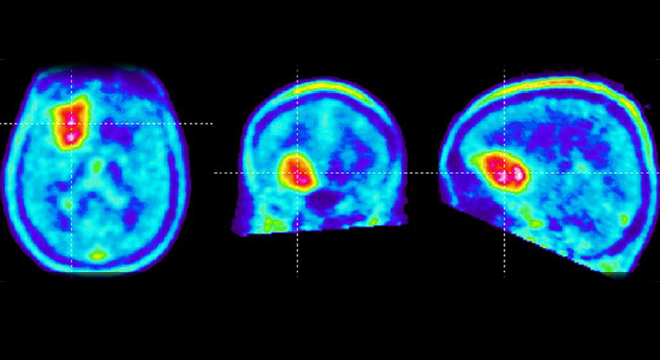

Hirntumor: Hirnscan durch MIR

• Bildgebung des Schädels und Hirns (Computertomographie oder MRI)